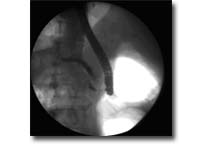

ERCP是将十二指肠镜经口插入十二指肠,寻找十二指肠乳头,再经活检通道置入造影导管并插入乳头,在X线透视下注入造影剂显示胆管、胰管的形态及异常变化。ERCP是胆道和胰腺疾病最为有效的诊断技术之一,也是胆胰疾病内镜下介入治疗的基础。包括:急性化脓性胆管炎、急性胆源性胰腺炎、胆总管结石、胆道蛔虫、梗阻性黄疸术前引流、胆瘘、胰瘘、慢性胰腺炎等。 |